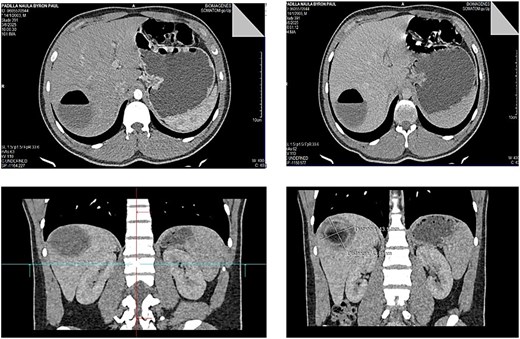

Contrast-enhanced abdominal computed tomography (CT) revealed a hydatid cyst, Gharbi type II, with an air-fluid level located in liver segment VII, measuring 5 cm in diameter and approximately 83 cc in volume. The air-fluid level was attributed to the previous puncture (Fig. 1).

Contrast-enhanced abdominal CT showing a Gharbi type II hydatid cyst with an air-fluid level in segment VII of the liver, measuring approximately 5 cm in diameter.